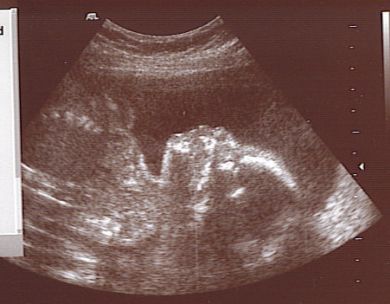

In de folder Zwanger NU leest u informatie over wat wel en niet mag in de zwangerschap, Bij welke alarmsignalen u moet bellen en hoe een prenatale controle er nu eigenlijk uitziet. In de folder Voeding tijdens de zwangerschap leest u wat u wel en juist niet mag eten tijdens de zwangerschap. De folder Echoscopie geeft aan wat een echo is, hoe dit plaatsvindt en wanneer het goed is om te laten maken. In de folder Zwangerschap en sport wordt aangegeven waarom het goed is om te sporten en welke sporten (zeer) geschikt zijn om mee door te gaan tot het einde van de zwangerschap. De folder Richtlijn controleschema zwangerschap geeft aan waar de controles minimaal uit behoren te bestaan.